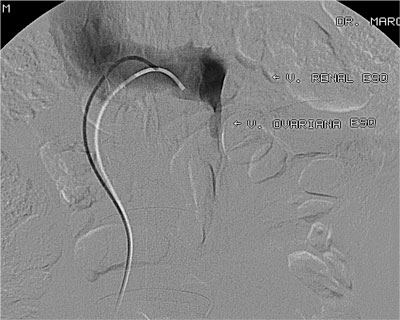

Paciente de 32 anos, feminino, nulípara, procurou consultório com queixa de fadiga nos membros inferiores e varizes vulvares que desciam até a face posterior da coxa direita. Realizado ultrassonografia com Doppler colorido de membros inferiores que mostrou normalidade das veias safenas e do sistema venoso profundo e identificou que as varizes da coxa direita corriam em direção a região genital. Solicitado ultrassonografia endovaginal com Doppler colorido que mostrou varizes pélvicas, sendo de maior calibre junto aos anexos à direita, com diâmetro máximo de 8 mm. A paciente foi submetida a flebografia que mostrou refluxo da veia ovariana direita com progressão do meio de contraste até a vulva. Realizado embolização da veia ovariana direita distalmente com polidocanol 3% para oclusão das colateriais pélvicas e com molas e histoacryl ao longo do seu tronco principal. A flebografia de controle mostrou oclusão completa da veia ovariana direita. Após 30 dias a paciente foi submetida à cirurgia convencional de varizes de membros inferiores através de mine-incisões da pele. Não houve intercorrências relacionadas ao procedimento endovascular e cirúrgico. No seguimento de 10 meses a paciente encontra-se assintomática e sem novas varizes, apresentando telangectasias residuais.